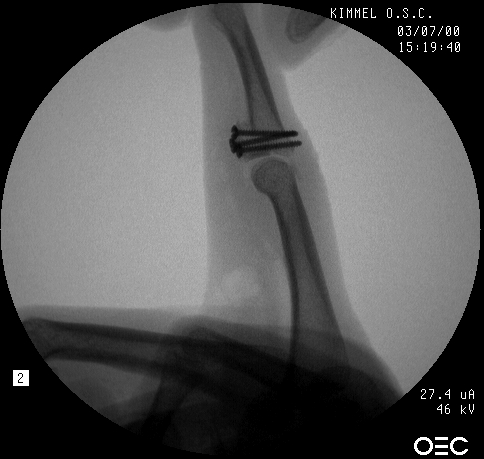

Here, the graft is in place and the joint has been reduced. The proximal two screws were then backed out slightly, and the volar plate was secured with sutures looped around the proximal two screws, which were then tightened back (not shown).

Final reconstruction.